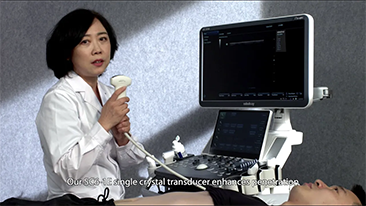

La gamme d'imagerie gÊnÊrale Resona de Mindray aide les cliniciens à obtenir des rÊsultats de diagnostic plus prÊcis et des traitements plus efficaces gr?ce à une gamme de sondes complète et à des outils cliniques avancÊs efficaces.